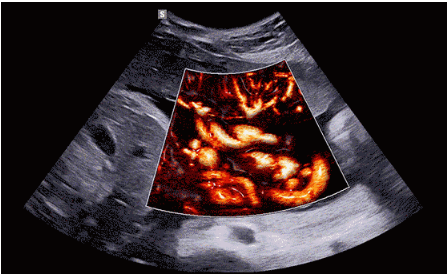

CrystalLive?是三星最新的超聲成像引擎,同時(shí)增強(qiáng)了2D圖像處理能力、3D渲染能力和彩色信號處理能力,能夠在復(fù)雜情況下提供出色的圖像性能,具備檢測外周血管、微循環(huán)血流的能力。

2D成像方面,Hera i10集成了包括ShadowHDR?、HQ-Vision?、ClearVision等多項(xiàng)具有三星“血統(tǒng)”的技術(shù),加強(qiáng)了圖像的陰影抑制、減少偽影、緩和模糊區(qū)。

3D/4D成像方面,Hera i 10通過結(jié)合先進(jìn)的圖像渲染技術(shù),著重加強(qiáng)了邊緣和小結(jié)構(gòu)的可視化能力。